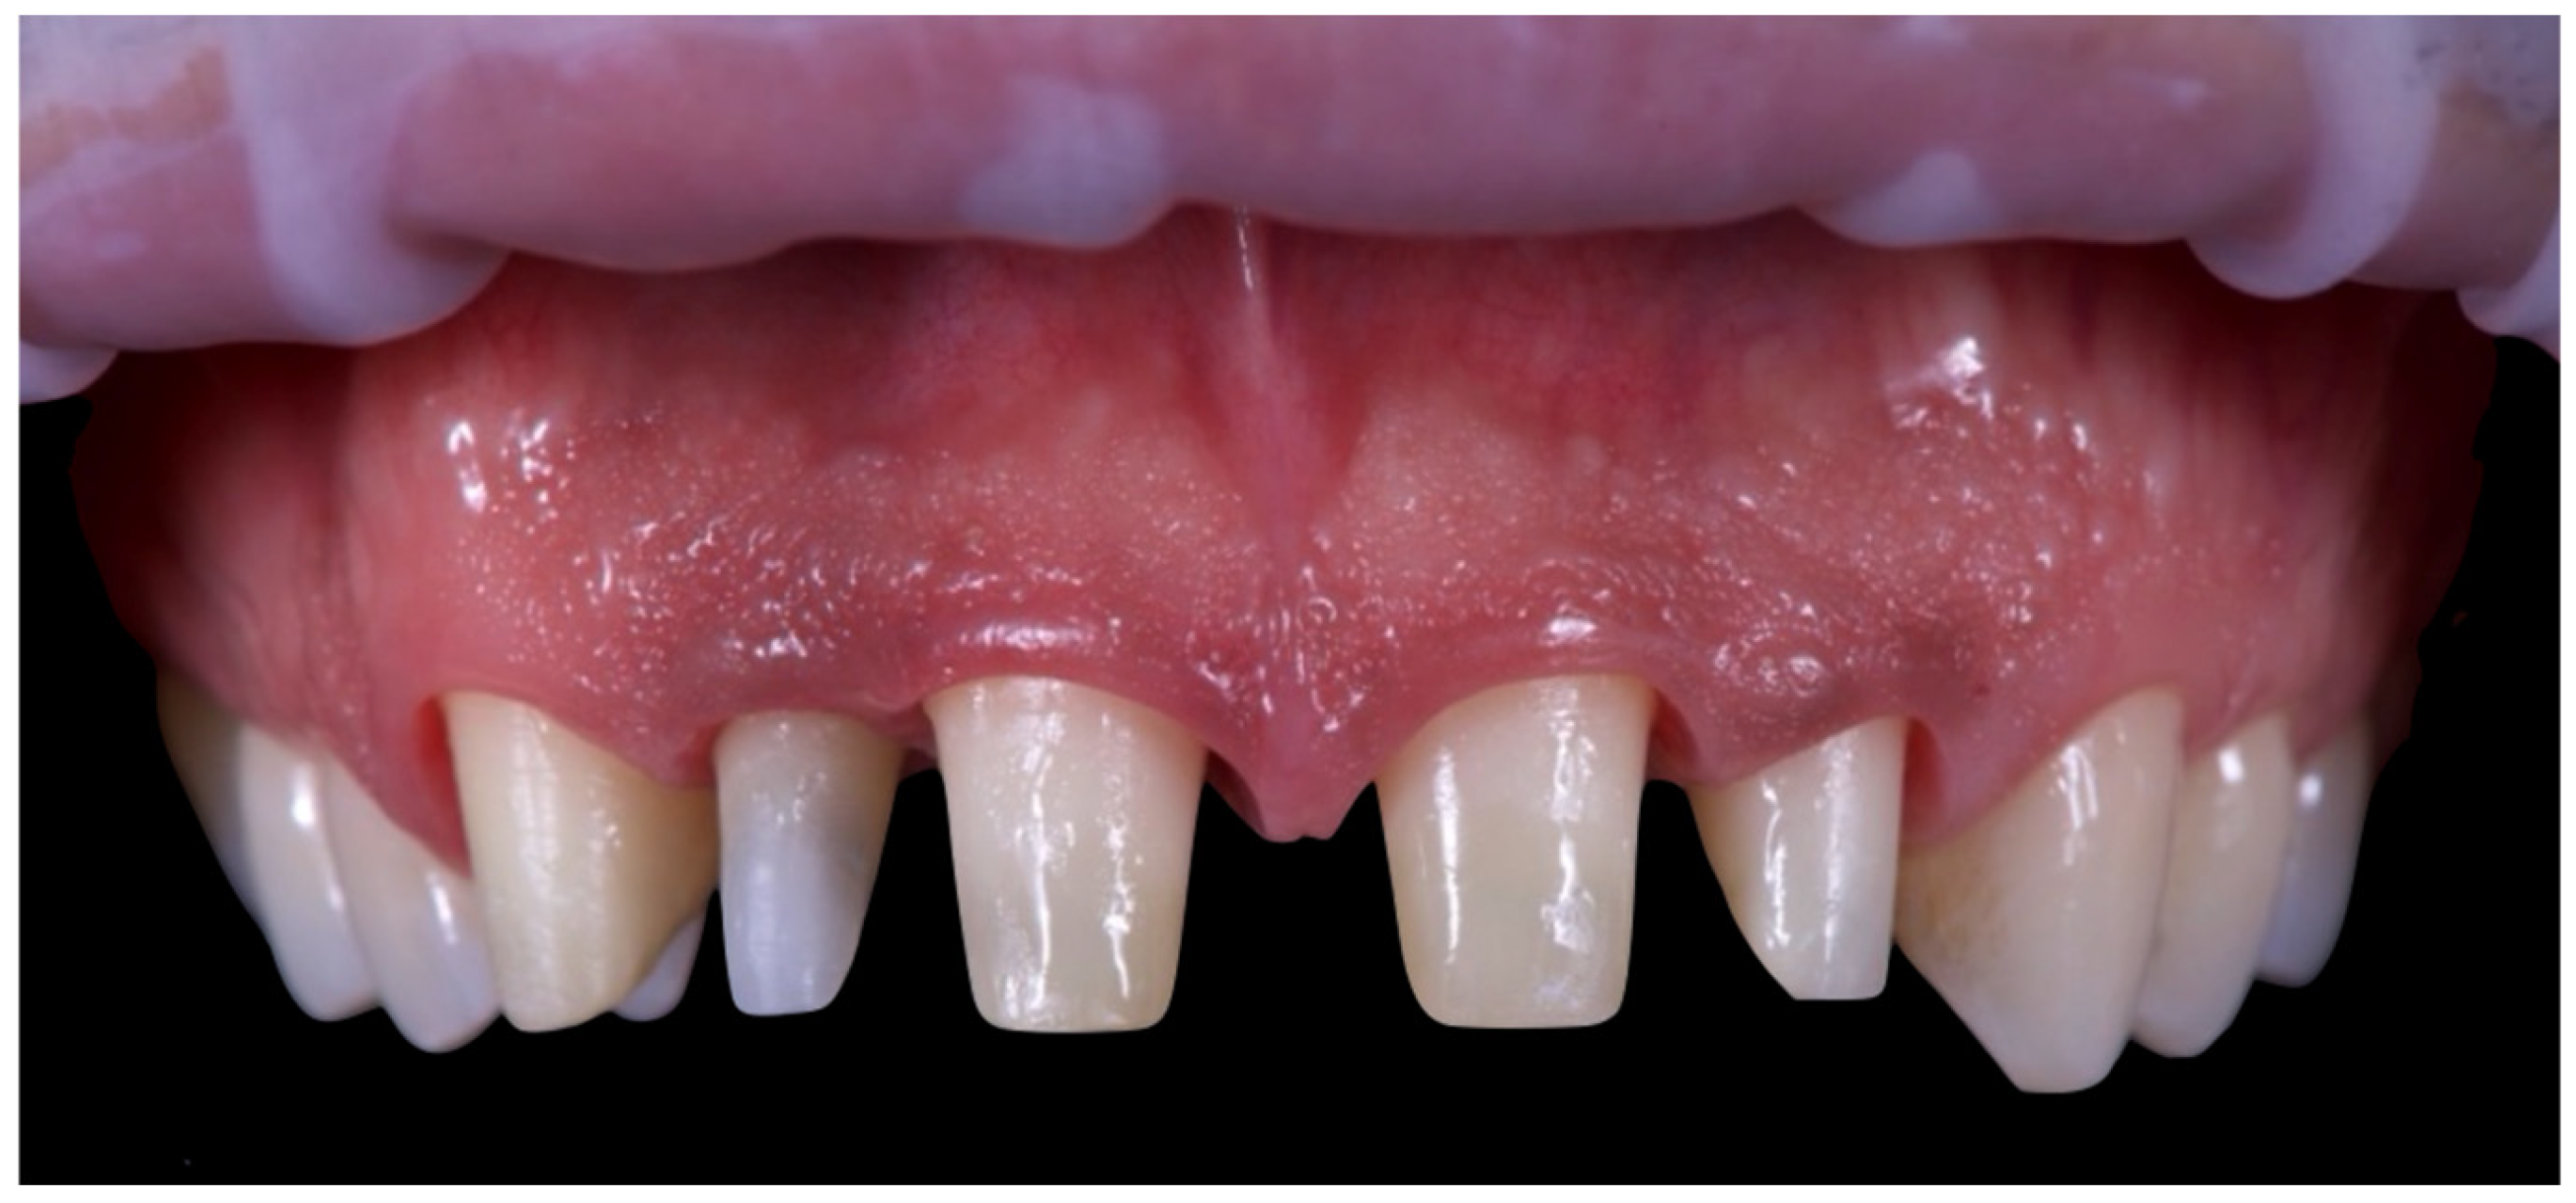

The first set of provisional restorations (Figure 10) was cemented using a non-eugenol temporary luting agent (Temp-Bond™ Clear, Kerr Dental, 8302 Kloten, Switzerland).

Figure 10. First provisional restoration.

These provisionals were segmented into two units (right and left) and maintained the existing interincisal diastema. The deep overbite was corrected, and an appropriate incisal guide was established. Both provisional restorations were progressively modified every 2–3 weeks to promote soft tissue adaptation, manage the emergence profile, and support the re-establishment of a new prosthetic cementoenamel junction (CEJ) over time. This approach also allowed for the continuous evaluation of the patient’s phonetics and functional dynamics. Approximately four months later, the preparations were refined under 16× magnification to optimise the emergence profiles and support soft tissue conditioning while preserving the edgeless finish line to enhance papillary stability and control (Figure 11).